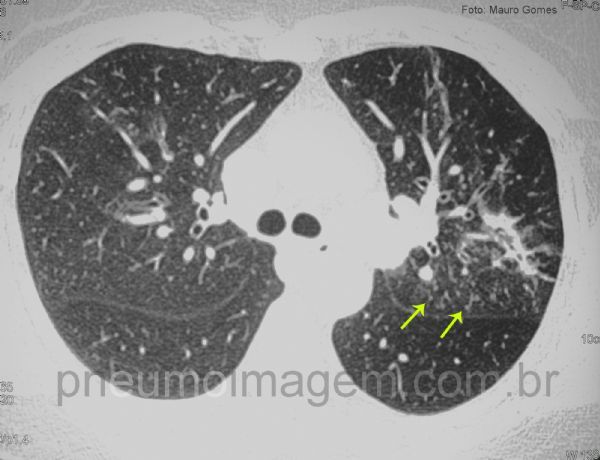

Opacidades apicais irregulares bilaterais, com predomínio no lobo superior esquerdo.

Alguns nódulos centrolobulares (setas amarelas) à esquerda, alguns à direita em menor número em topografia de lobo médio.

Irregular bilateral apical opacities, predominantly in the left upper lobe.

Some centrilobular nodules (yellow arrows) on the left, some right on the topography of the middle lobe.